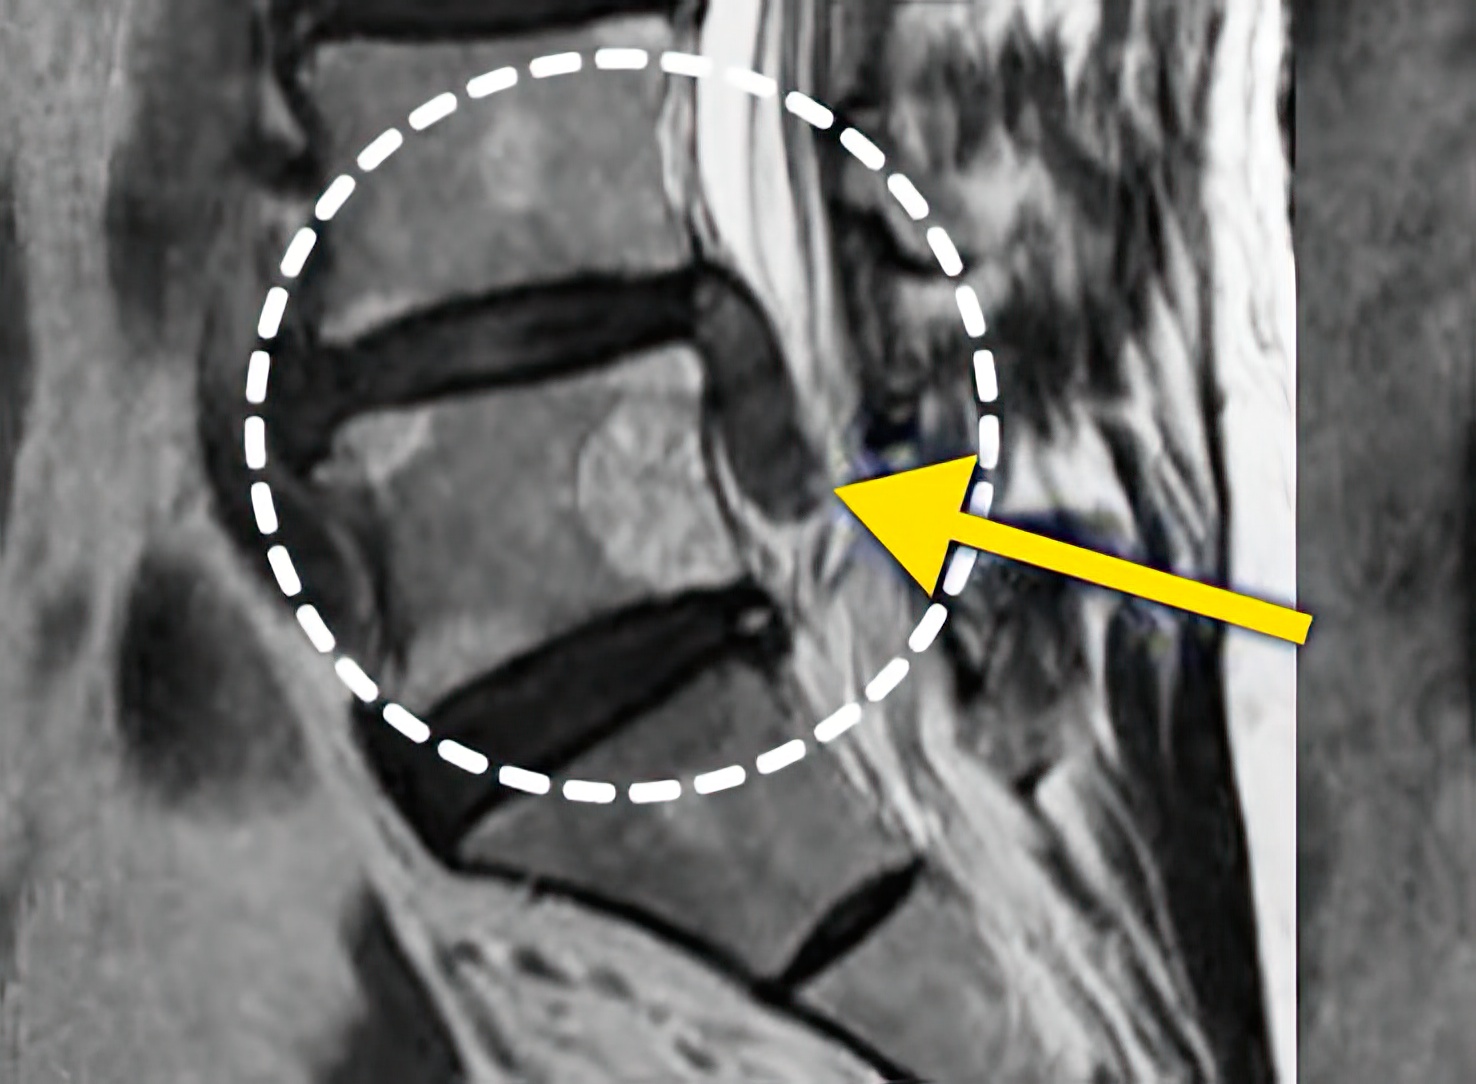

오랜 시간 동안 진행되어온 퇴행성 척추질환(퇴행성디스크, 척추관 협착증), 뼈의 구조적인 이상(척추분리증, 척추전방전위증, 척추이분증) 등은 병의 진행 상태에 따라 치료 기간이 달라질 수 있습니다.